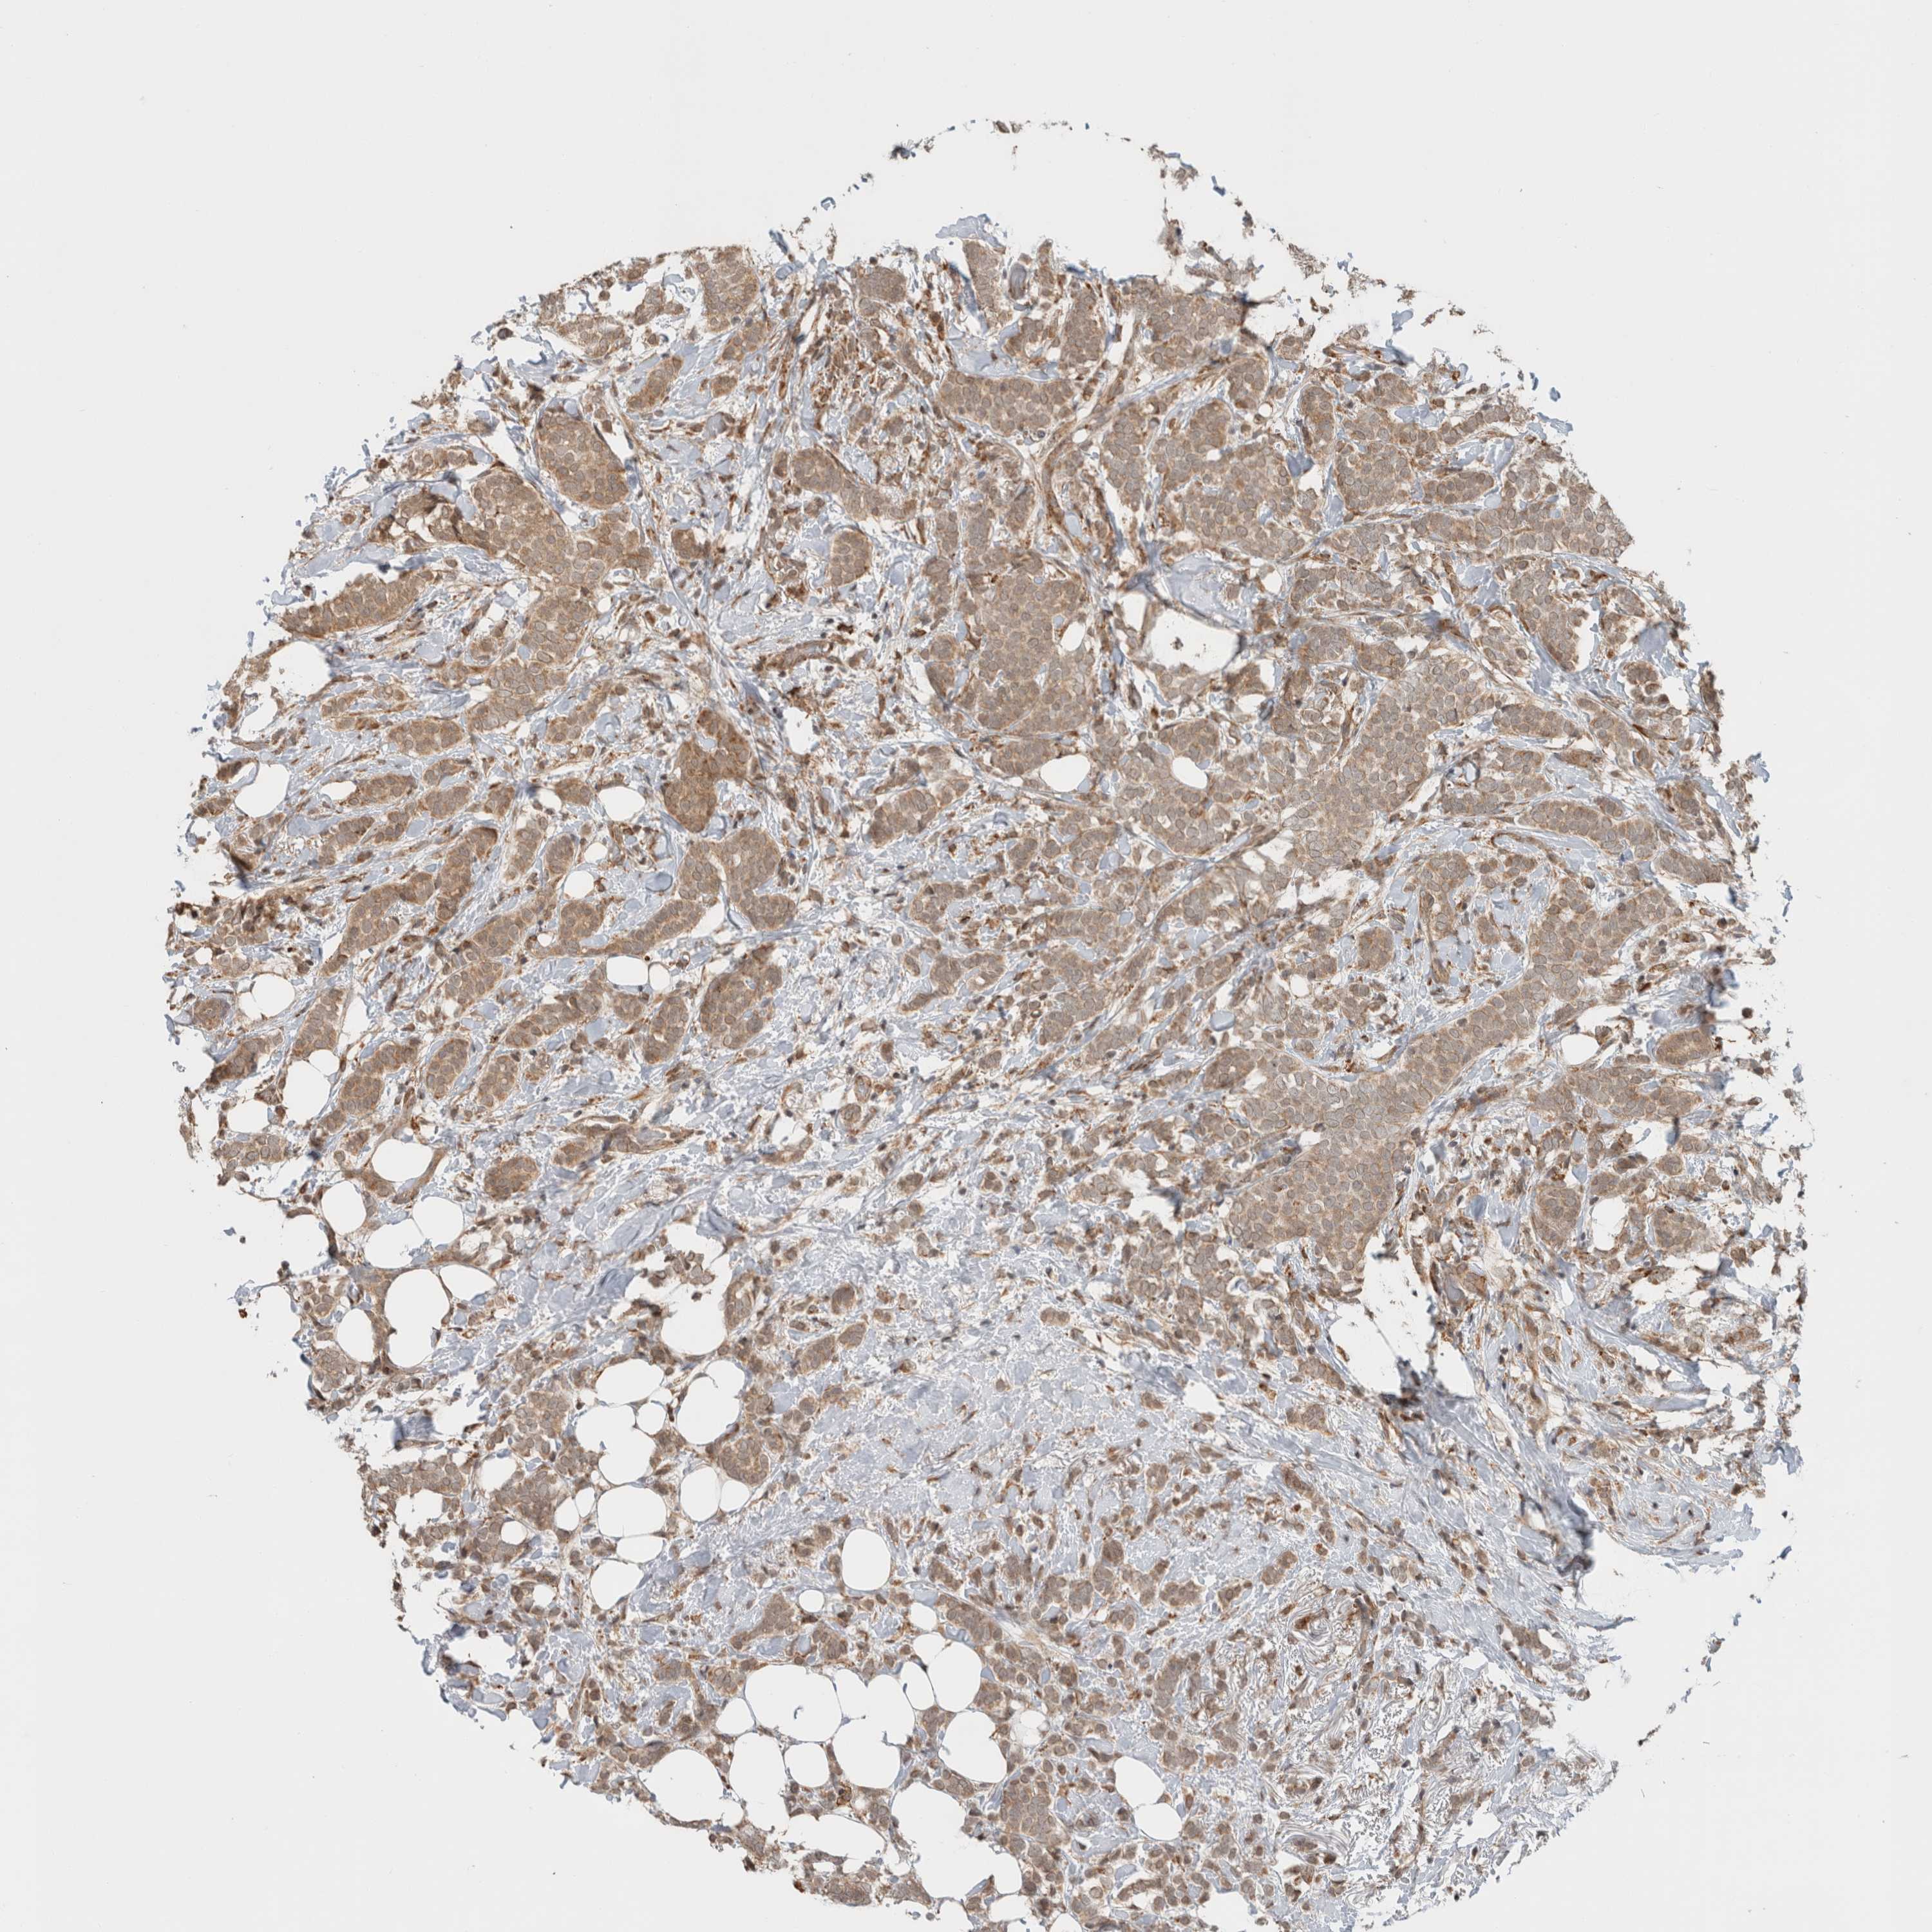

CANCER BREAST CANCER Show tissue menu

BRCA TCGA BRCA VALIDATION PROTEIN EXPRESSION

Breast cancer

Human cancer

MS4A7 is not prognostic in Breast Invasive Carcinoma (TCGA)